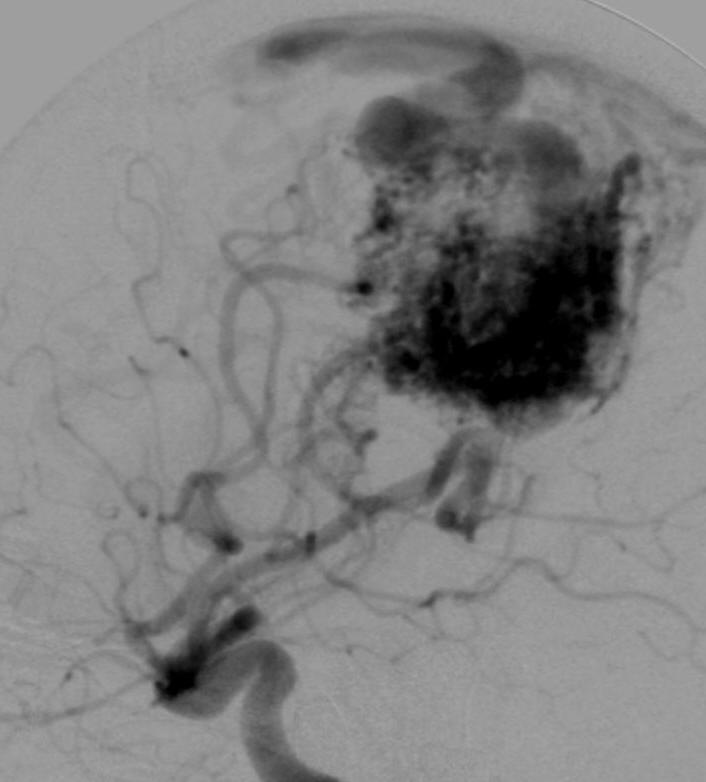

病例1 - 13: 一口气"唱"血管造影诊断_______测试

病例2